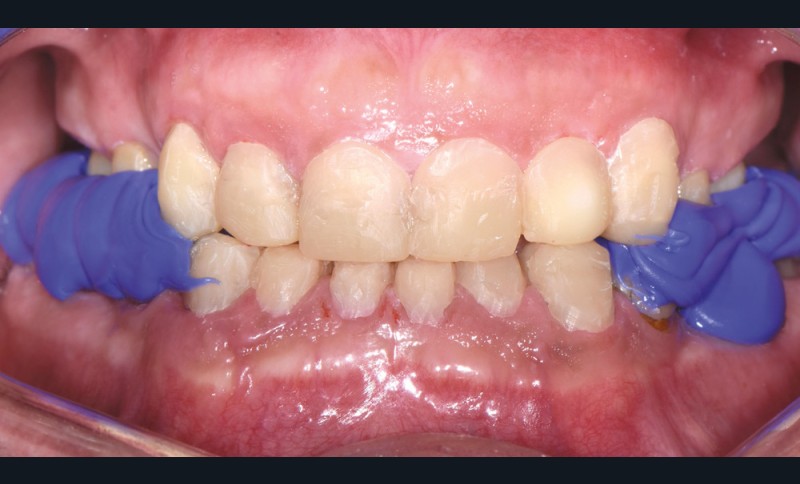

Au vu du contexte para-fonctionnel et de l’étendue de la perte tissulaire, des coiffes périphériques minimalement invasives ont été choisies afin de restaurer l’esthétique et la fonction. Actuellement, aucun consensus n’est fait sur le choix du matériau d’infrastructure à privilégier. Les matériaux hybrides usinables présentent des propriétés mécaniques, physiques et biologiques intéressantes en contexte d’usure sévère (e.g., module d’élasticité, résistance à la propagation de fêlures, facilité de réintervention). Une réhabilitation globale avec remontée de dimension verticale d’occlusion (DVO) par l’intermédiaire de coiffes composites renforcés en nano-céramiques est décrite.